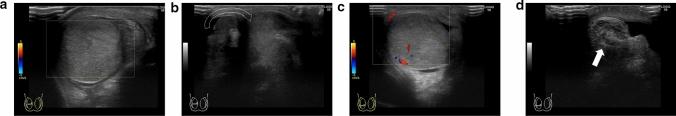

Testicular torsion is a urological emergency caused by the loss of testicular tissue due to ischemic damage. Rapid diagnosis and urgent treatment play a crucial role in the management of testicular torsion. Manual detorsion can be performed at the bedside, thereby reducing the duration of ischemia. Recent studies have reported the use of point-of-care ultrasonography for diagnosing testicular torsion; however, no review article has focused on the ultrasonographic findings pertaining to manual detorsion. This review describes the diagnosis of testicular torsion and the ultrasonographic indications for manual detorsion. Spermatic cord twisting or the whirlpool sign, absence of or decreased blood flow within the affected testis, abnormal testicular axis, abnormal echogenicity, and enlargement of the affected testis and epididymis due to ischemia are the sonographic findings associated with testicular torsion. The following findings are considered indications for manual detorsion: direction of testicular torsion, i.e., inner or outer direction (ultrasonographic accuracy of 70%), and the degree of spermatic cord twist. The following sonographic findings are used to determine whether the treatment was successful: presence of the whirlpool sign and the degree and extent of perfusion of the affected testis. Misdiagnosis of the direction of manual detorsion, a high degree of spermatic cord twisting and insufficient detorsion, testicular compartment syndrome, and testicular necrosis were found to result in treatment failure. The success of manual detorsion is determined based on the symptoms and sonographic findings. Subsequent surgical exploration is recommended in all cases, regardless of the success of manual detorsion.

睾丸扭转是一种泌尿外科急症,由缺血性损伤导致睾丸组织丧失引起。快速诊断和紧急治疗在睾丸扭转的管理中起着至关重要的作用。床边手动复位可减少缺血持续时间。最近的研究报告了使用即时超声检查来诊断睾丸扭转,但没有综述文章专门关注手动复位的超声表现。本文描述了睾丸扭转的诊断和手动复位的超声指征。精索扭曲或漩涡征、受累睾丸内无血流或血流减少、睾丸轴异常、回声异常以及缺血引起的受累睾丸和附睾增大是与睾丸扭转相关的超声表现。以下发现被认为是手动复位的指征:睾丸扭转的方向,即内旋或外旋(超声准确性为 70%)和精索扭转的程度。以下超声表现用于确定治疗是否成功:漩涡征的存在以及受累睾丸的灌注程度和范围。手动复位方向的误诊、精索扭转程度高和复位不足、睾丸间隔综合征和睾丸坏死均导致治疗失败。手动复位的成功与否取决于症状和超声表现。无论手动复位是否成功,都建议进行后续的手术探查。